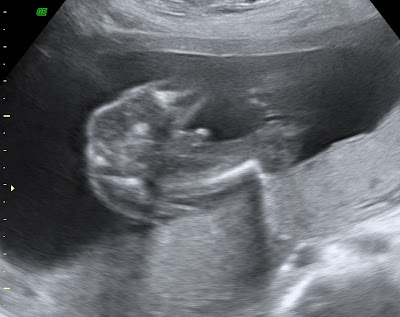

The appointment went great! Everything looked normal. The baby's heartbeat was 144 bpm. I also got a few pictures, you know I love those!

The 3D ultrasound pic!

And the money shot!

Can you tell what gender the baby is? I could. That should say something! Have a wonderful day, everyone!